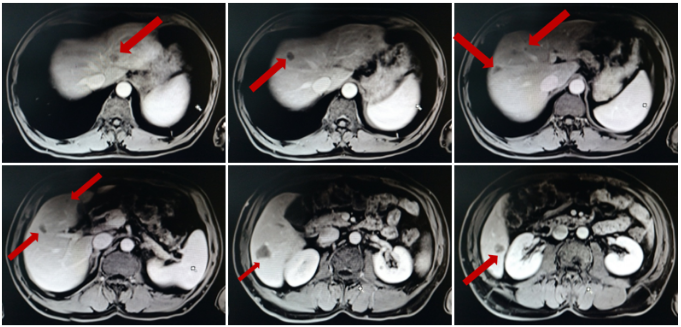

2017.12.20-2018.03.05行4周期FOLFOX4联合贝伐珠单抗治疗。

期间出现II度白细胞下降,II度血小板下降,II度肝功能不良。

化疗前后病灶变化情况

2018.03.15患者现疗效评价为PD,且患者体能状态较前下降(ECOG 1分),化疗期间出现II度骨髓抑制及肝功能不良,建议更改瑞戈非尼治疗。